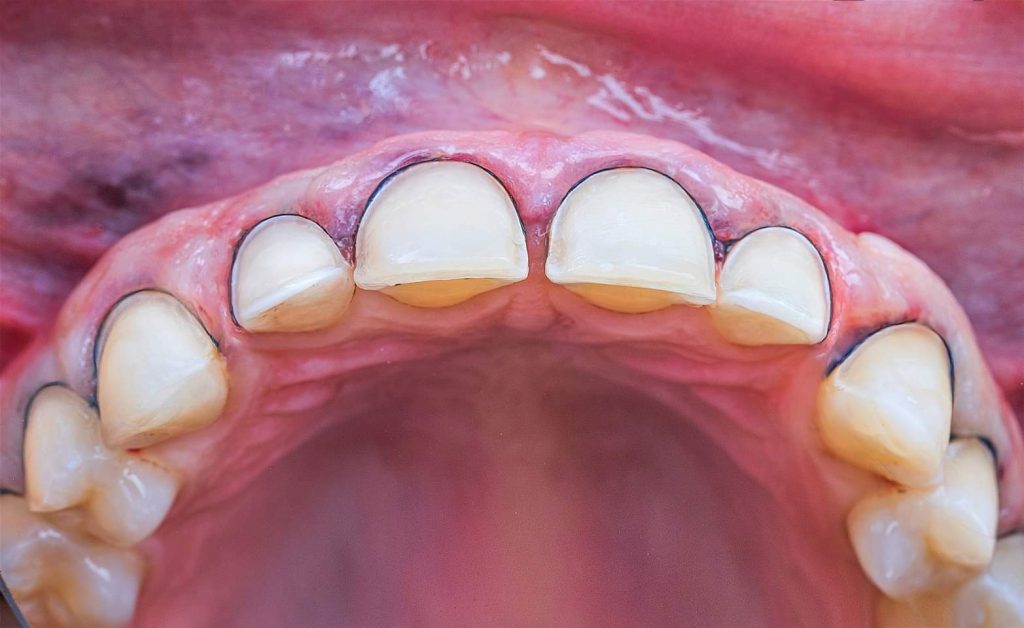

The case presented in this case report is for a 27-years-old female patient with a chief complaint of aesthetic correction for her smile. The patient was unhappy with her smile. After clinical examination, there were previous old composite veneering done poorly and incorrectly to close the multiple interdental spacing. After discussing the various treatment options (i.e., orthodontic treatment, direct, or indirect veneers), indirect ceramic veneering was selected. The step-by-step treatment protocol is presented in the images below.